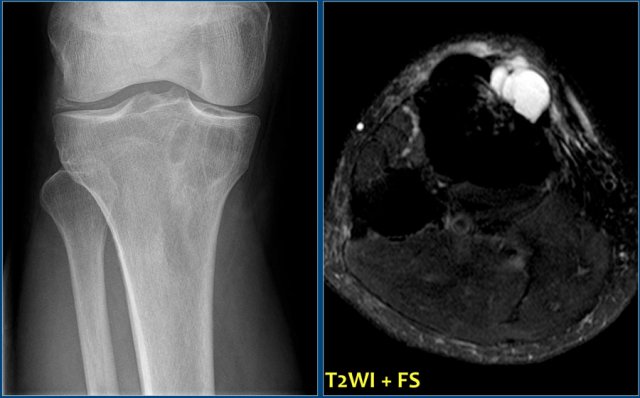

On the left more examples of GCT around the knee.

Notice that most of these lesions are well-defined and located in the epiphysis and extend into the metaphysis.

Some extend onto the articular surface (yellow arrow and small red arrows).

The lesion on the upper right has an ill-defined border with a broad zone of transition (blue arrow).